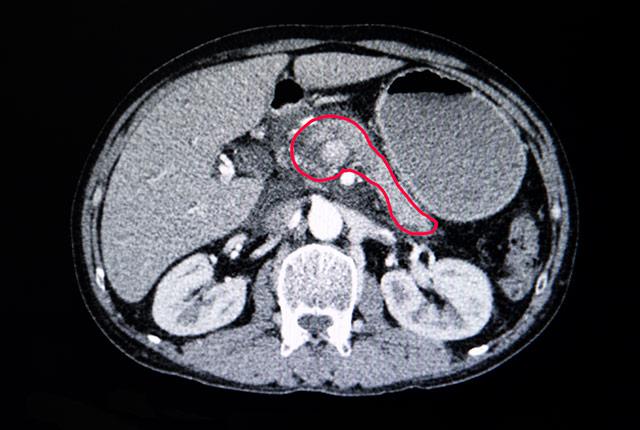

In a paper published April 2 in the journal Clinical Cancer Research, the researchers report that they found such T cells within pancreatic tumors and determined that they can be activated to attack and kill cancer cells. They studied pancreatic ductal adenocarcinoma, the most common and most deadly pancreatic cancer.

Much of what is known about the immune system’s reaction to pancreatic cancer comes from mouse studies. In this study, however, researchers studied immune-cell behavior in human pancreatic tumor tissue. They used small, cylindrical core samples taken from tumors removed during surgery at University of Washington Medical Center. The cylinders were cut into 250 micron-thick discs that were maintained in nutrient-rich fluid and studied under the microscope for up to one week.